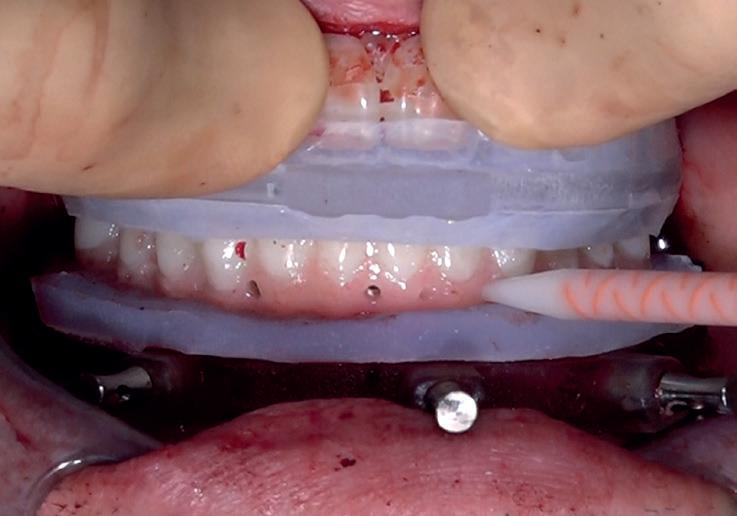

RECUPERAREA planului implantar original. Dacă unul sau mai multe implanturi planificate eșuează, perspectiva reimplantării în locația compromisă poate fi simplificată prin transformarea ghidului chirurgical la nivel osos într-un ghid chirurgical suportat de implanturi în momentul intervenției chirurgicale primare.

REABILITAREA implanturilor în zona estetică. Acest articol detaliază două cazuri rezolvate prin tehnica extracției parțiale, finalizate fără grefarea compartimentului dintre implant și scut, și monitorizate cinci ani, dovedind stabilitatea volumetrică a țesuturilor moi și dure în timp.